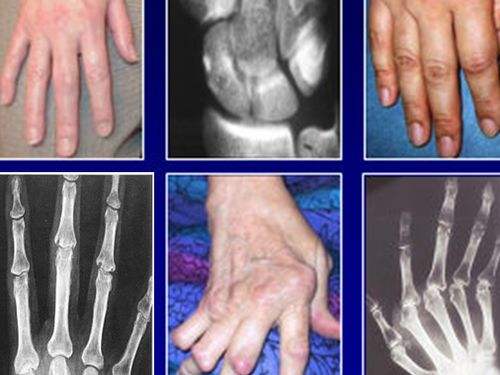

风湿性关节炎常见累及大关节(膝关节、肘关节等),不造成关节的畸形。还有环形红斑、舞蹈症、心脏炎的症状。类风湿关节炎往往侵犯小关节(尤其是掌指关节、近端指间关节、腕关节),也会侵及其他大小关节,晚期往往造成关节的畸形。

还可出现类风湿结节和心、肺、肾、周围神经及眼的内脏病变。

5.手部有典型的类风湿性关节炎的放射学改变。